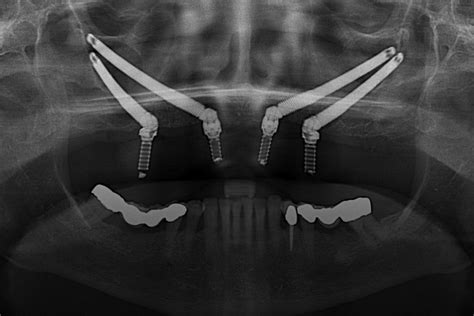

Desde implantes dentales y dientes fijos en 24 horas, hasta técnicas avanzadas como los implantes cigomáticos para pacientes con poco hueso, ofrecemos soluciones personalizadas para cada necesidad.

Utilizamos planificación digital 3D, cirugía guiada y contamos con laboratorio propio para garantizar tratamientos más rápidos, precisos y personalizados. Nuestros odontólogos cuentan con formación continua y amplia experiencia clínica.